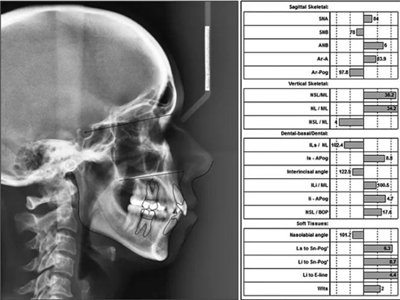

頭影測量分析,SNA角84°,ANB角6°,高角型,詳見下表。

患者側貌改善,下唇唇肌緊張消失,上下唇可自然閉合。磨牙及尖牙關系糾正至I類,覆合覆蓋正常。上下頜弓型糾正至卵圓形,牙弓寬度增加。頭影測量分析示SNA角81.8°,ANB角3°。頭影測量重疊圖示下頜骨向后旋轉,垂直面高度略有增加。